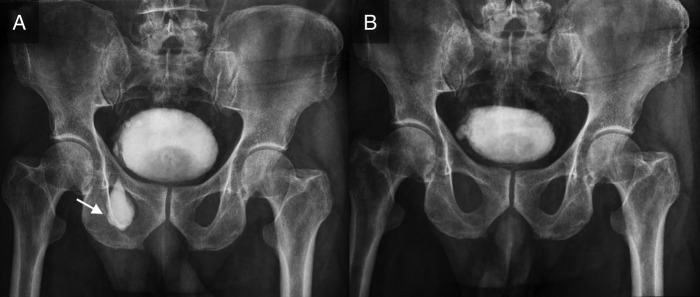

图 2

(A) 膀胱憩室(箭头)的大图,充满造影剂并在腹股沟管中下降。 (B) 排尿后图像中膀胱憩室完全排空。